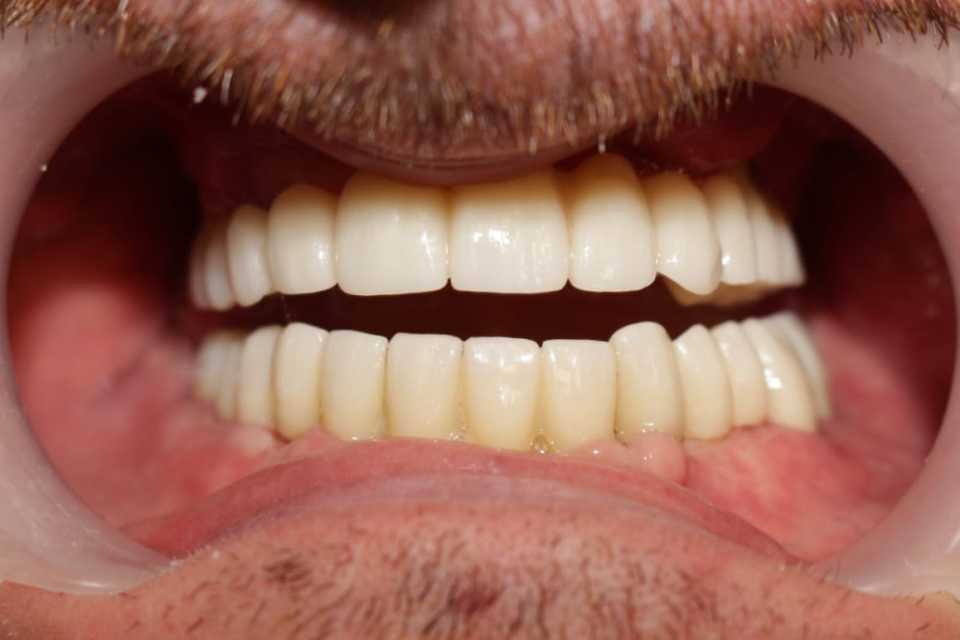

Reabilitarea orala funcțională și estetică, s-a realizat cu ajutorul unei lucrări fixe cimentate la nivelul maxilarului din ceramica pe zirconiu și a 3 lucrări din ceramica pe zirconiu fixe cimentate la nivelul mandibulei.

Cazul a fost o adevărată provocare, nu numai chirurgical, dar și protetic. Prin prisma resorbției osoase severe maxilare în zona frontală și a purtării îndelungate a protezelor mobile, la momentul consultului inițial, pacientul prezenta un etaj inferior al feței micșorat cu profil concav .